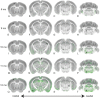

Neurodegenerative tauopathies are hypothesized to propagate via brain networks. This is uncertain because we have lacked precise network resolution of pathology. We therefore developed whole-brain staining methods with anti-p-tau nanobodies and imaged in 3D PS19 tauopathy mice, which have pan-neuronal expression of full-length human tau containing the P301S mutation. We analyzed patterns of p-tau deposition across established brain networks at multiple ages, testing the relationship between structural connectivity and patterns of progressive pathology. We identified core regions with early tau deposition, and used network propagation modeling to determine the link between tau pathology and connectivity strength. We discovered a bias towards retrograde network-based propagation of tau. This novel approach establishes a fundamental role for brain networks in tau propagation, with implications for human disease.